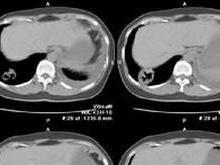

2、CT能分辨出普通X線中不能顯示的肺部結構,且經CT引導下進行經皮肺活檢定位準確安全度大。